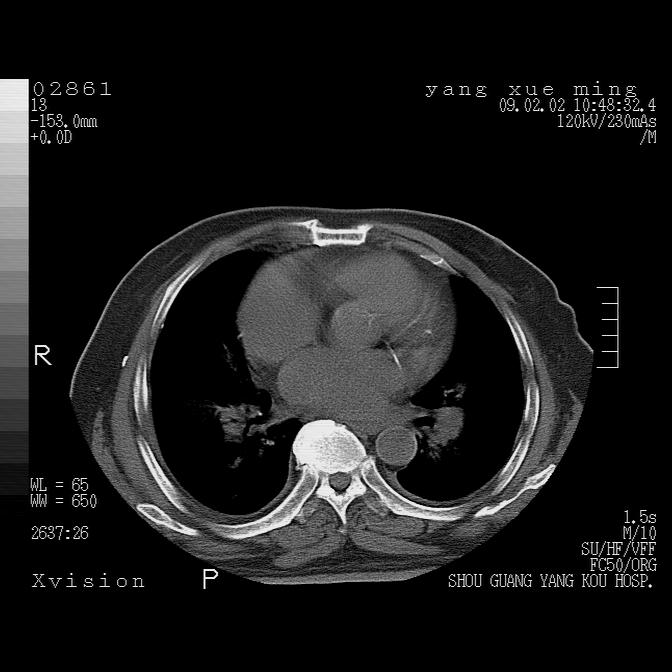

以下是引用zbp537在2009-2-3 19:08:00的发言:[br]我诊断为肺泡性肺水肿。[br]诊断依据:[br]1、心影普遍增大,肺血管增粗,并见絮状高密度影,肺门改变显著。[br]2、临床上表现胸闷咳嗽,无发烧,不是一个典型的肺部感染的病史。

以下是引用lkc8963在2009-2-3 20:11:00的发言:[br]1)右上肺陈旧病灶。2)右下肺团块及团片影,影像表现符合感染。3)左心增大,左冠脉钙化,符合冠心病。4)双侧肺门扩大,以左侧为著,肺动脉干略粗,左上肺局限性气肿,为谨慎起见,需除肿瘤,建议增强。

以下是引用lkc8963在2009-2-3 20:11:00的发言:[br]1)右上肺陈旧病灶.2)右下肺团块及团片影,影像表现符合感染.3)左心增大,左冠脉钙化,符合冠心病.4)双侧肺门扩大以左侧为著,肺动脉干略粗,左上肺局限性气肿,为谨慎起见,需除肿瘤,建议增强.